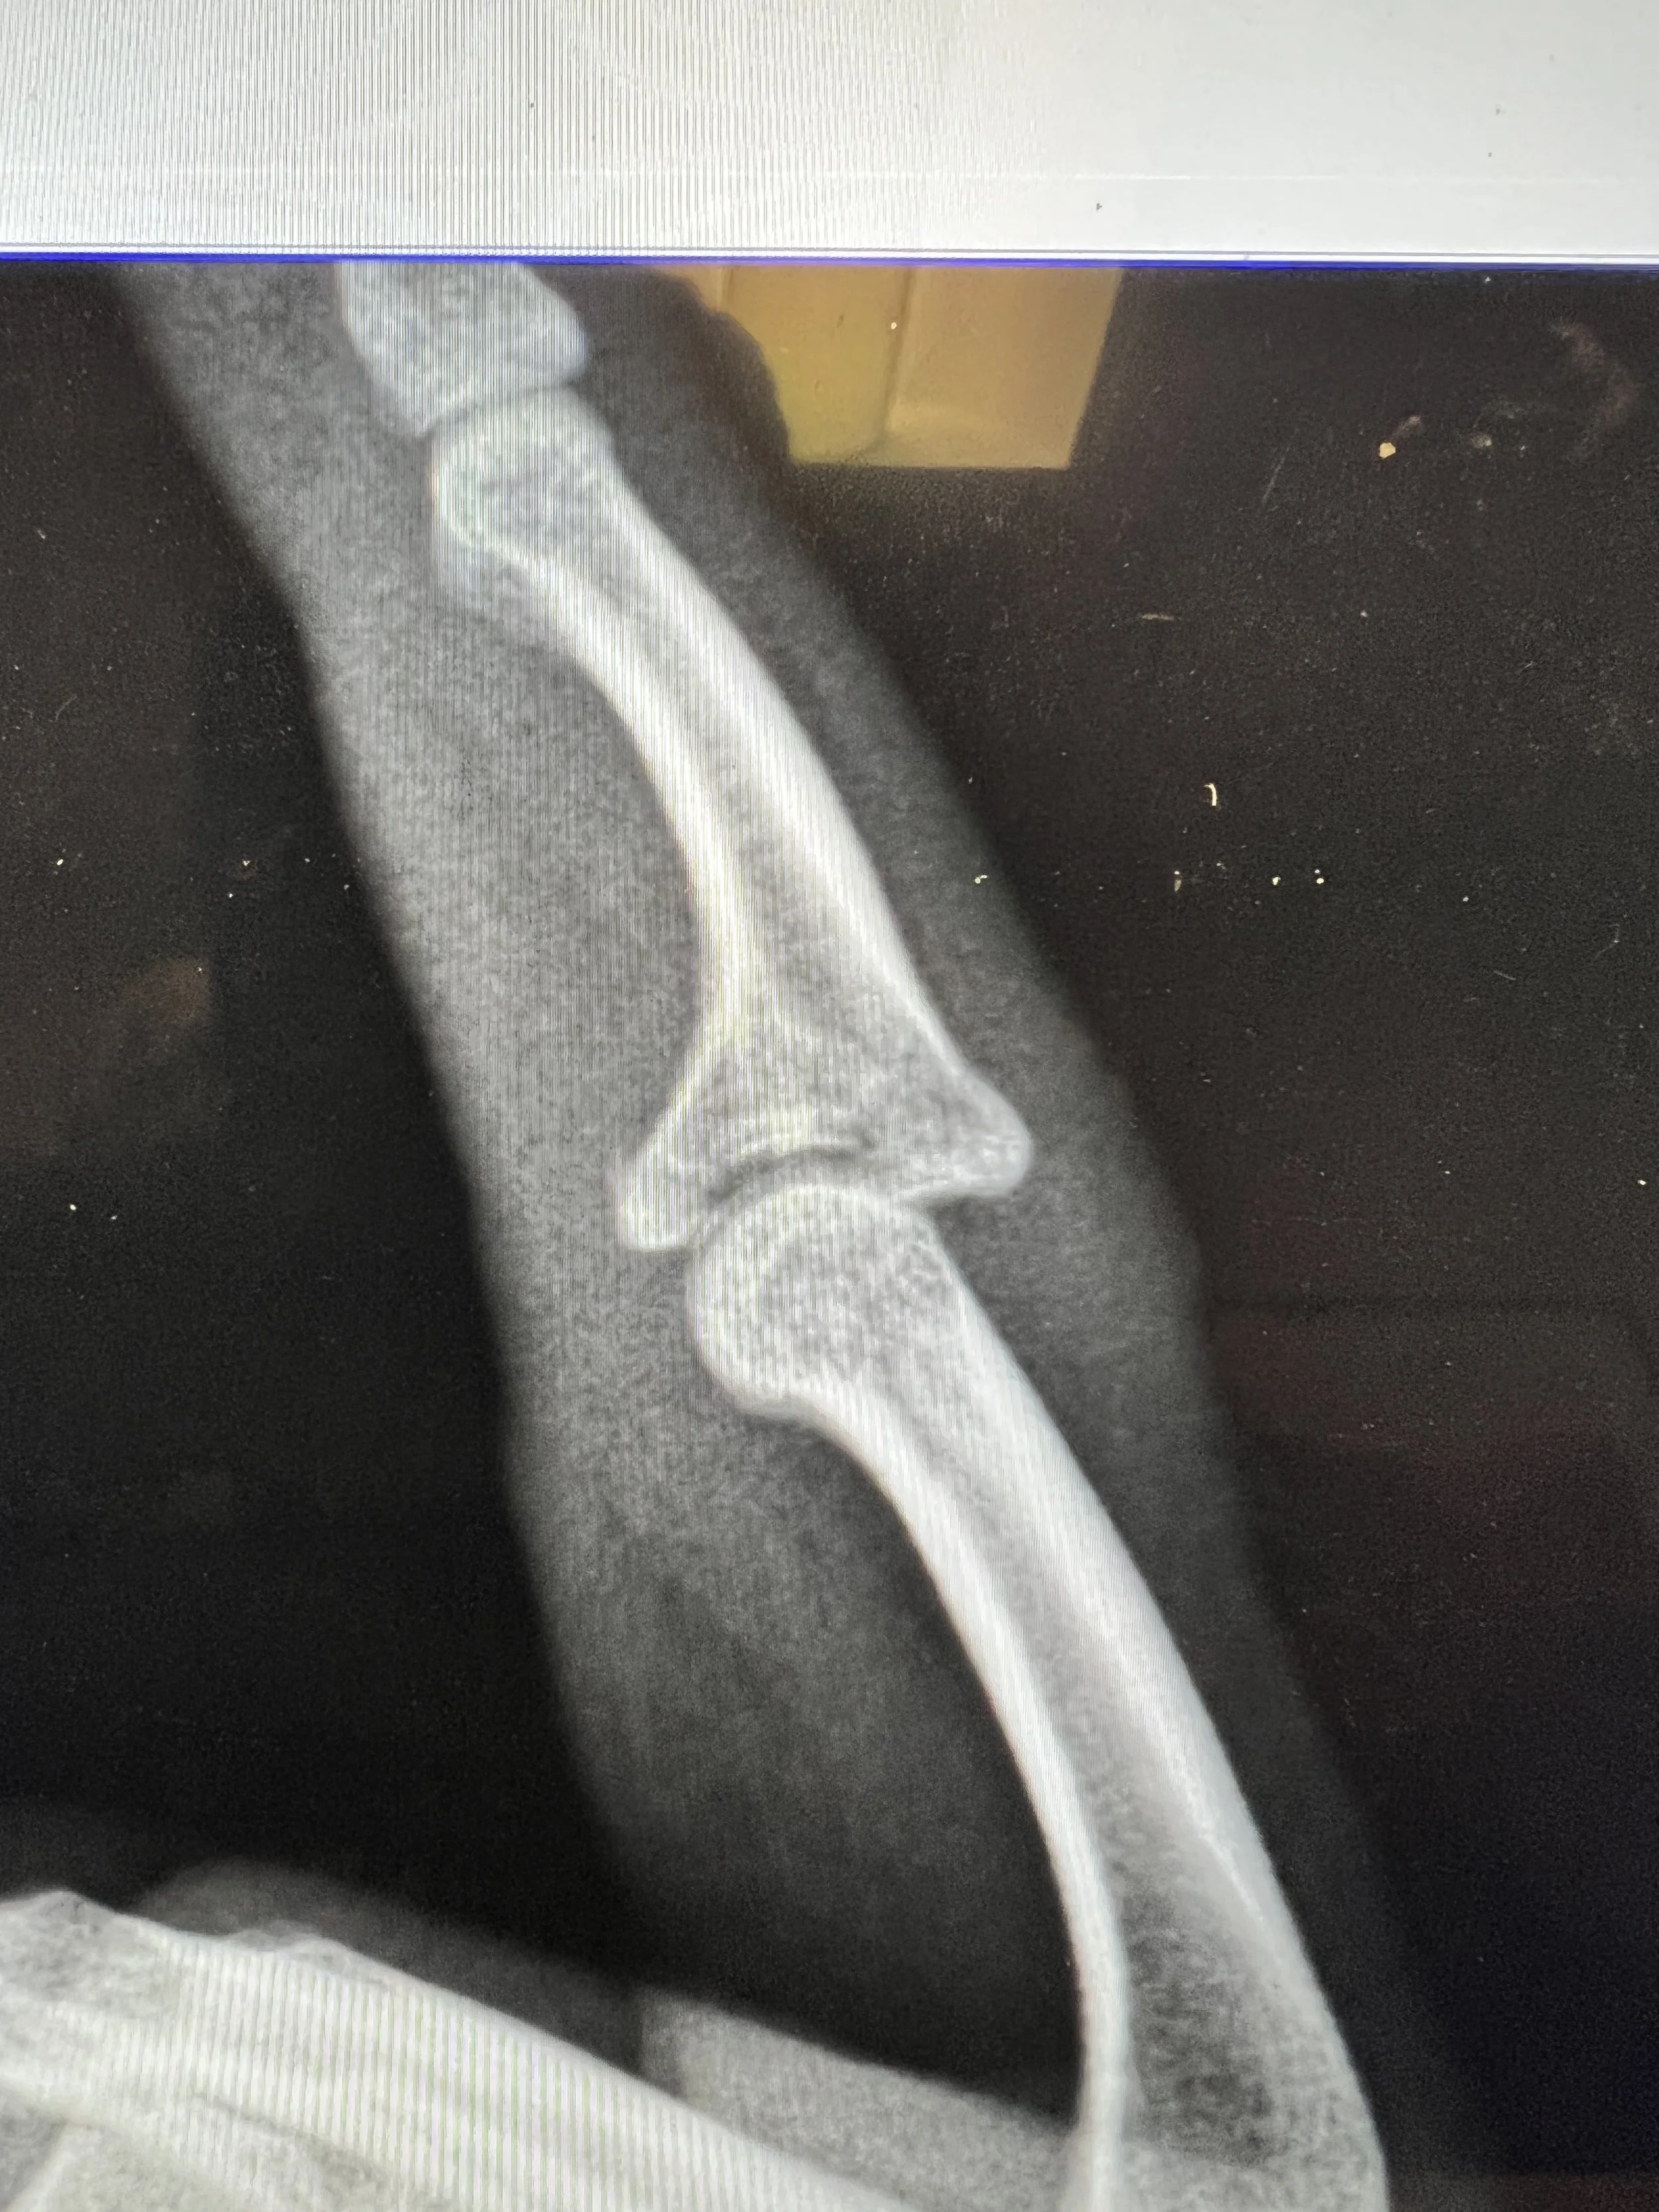

Finger Proximal Interphalangeal (PIP) Joint Dislocation Rehab My Patient Jammed Finger On Xray It causes pain, swelling and tenderness in your finger. Diagnosis is made clinically and mri may be required for. A jammed finger or sprained finger is usually the result of an injury or fall. If you are unable to wiggle it, it may be broken or dislocated and may. Physical examination is performed to check finger position, movement, pain and. Jammed Finger On Xray.